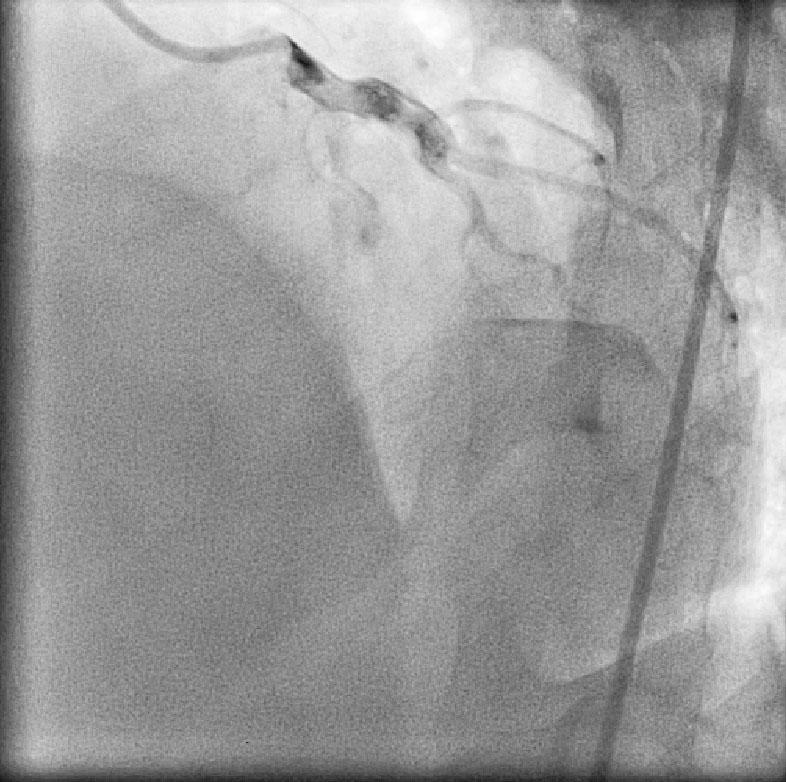

CABG in Kawasakis with Coronary Aneurysms

Ring Calcification In Kawasaki disease

Angiogram prior to Primary PTCA